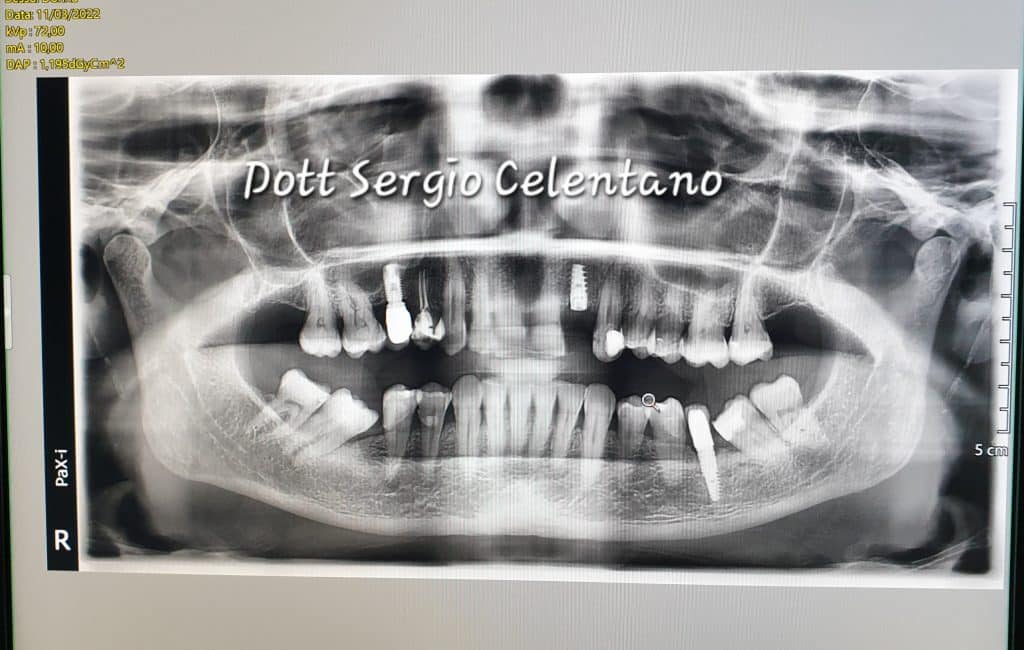

Paziente donna con mobilità di grado severo in zona 2.2

Si è optato per l’inserimento di impianto post estrattivo.

Dopo lo studio del caso e la scelta del miglior impianto da inserire, nella stessa seduta, al paziente è stato estratto l’elemento dentario danneggiato e inserito fixture in titanio apponendo un elemento provvisorio in attesa della guarigione.